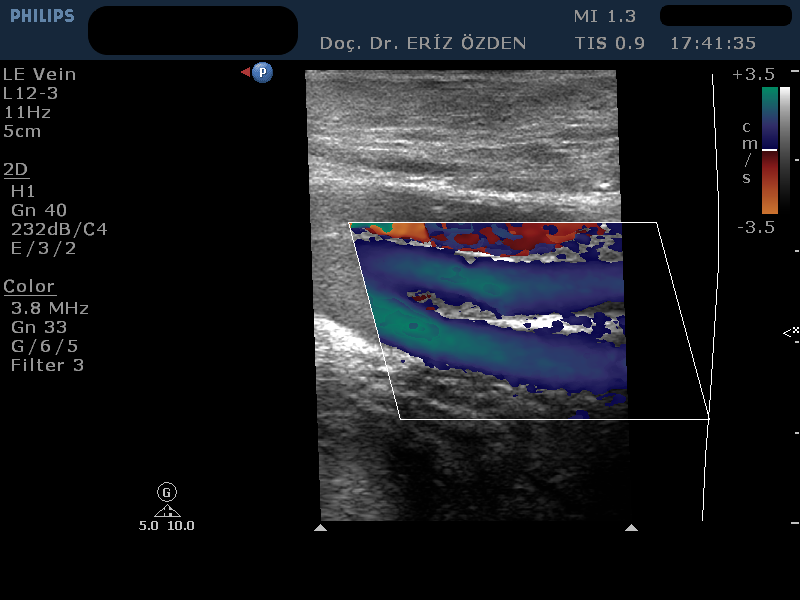

Bacak Venöz Doppler Nasıl Yapılır? Ultrasonografi cihazı Renkli Doppler özelliğine sahipse, damarların içindeki kan akımını renkli olarak görmek mümkündür. Renkli Doppler Ultrason adı verilen bu yöntem sayesinde damarlardaki daralmalar, pıhtılar ve tıkanıklar saptanır. Kan akım hızına yönelik ölçümler yapılır. Bacak atar ve toplar damarlarındaki problemlerde Renkli Doppler çok sık kullanılır. Toplardamarların içindeki kan akımı renkli olarak görülür. Kan akımının yönü, miktarı, damarlada geriye kaçış olup ulmadığı ve en önemlisi toplardamarlar içindeki pıhtılar tespit edilir. İnceleme önce hasta sırt üstü yatırılarak başlar. Kasıktan başlayarak ayak bileğine kadar tüm toplardamarlar incelenir. Bunun için hastanın bacağına jel sürülür ve ultrason cihazının başlığı cildinin üzerine dokundurulur. İnceleme hiç acı vermez. Renkli doppler yöntemiyle bacak içindeki toplardamarlar renkli olarak görülür. Kasıltan ayak bileğine kadar bacakta bulunan çok sayıda toplardamarın hepsi, ayrı ayrı, santim santim takip edilerek, içindeki kan akımı, pıhtı varlığı, damar yetmezliği açısından incelenir. Devamında hasta yüzüstü yatırılarak diz ve bacak arkasında yer alan toplardamarlar incelenir. Ardından hasta dik pozisyona getirilir. Bu aşamada, hasta dik duruken, yer çekimi ile damarlarda yetmezlik ortaya çıkıp çıkmadığına bakılır.

Bacak Venöz Renkli Doppler Tetkiki Neden Yapılır? Venöz Renkli Doppler tetkiki, bacak toplardamarlarındaki varislerin, yetmezliklerin ve pıhtı oluşumlarının araştırılmasında kullanılır. Uzun süre ayakta durarak çalışanlarda, ileri yaşlardaki kişilerde, çoğunlukla da bilinmeyen nedenlerle bacak toplardamarlarında yetmezlik olabilir. Normalde toplardamarlardaki kirli kan, devamlı olarak yukarı, yani kalbe doğru akar. Hastanın ıkınması, öksürmesi, uzun süre ayakta kalması gibi durumlarda kan geriye doğru akmamalıdır. Damar içindeki ince kapakçıklar geriye akımı önler. Kanın geriye doğru kaçış göstermesine reflü akım denir. Bu durum venöz yetmezlik olarak adlandırılır ve bacaklarda şişme ya da varislerin oluşmasına neden olabilir. Hangi damarlarda, hangi derecede yetmezlik olduğu Venöz Renkli Doppler Ultrasonografi tetkiki ile anlaşılır.